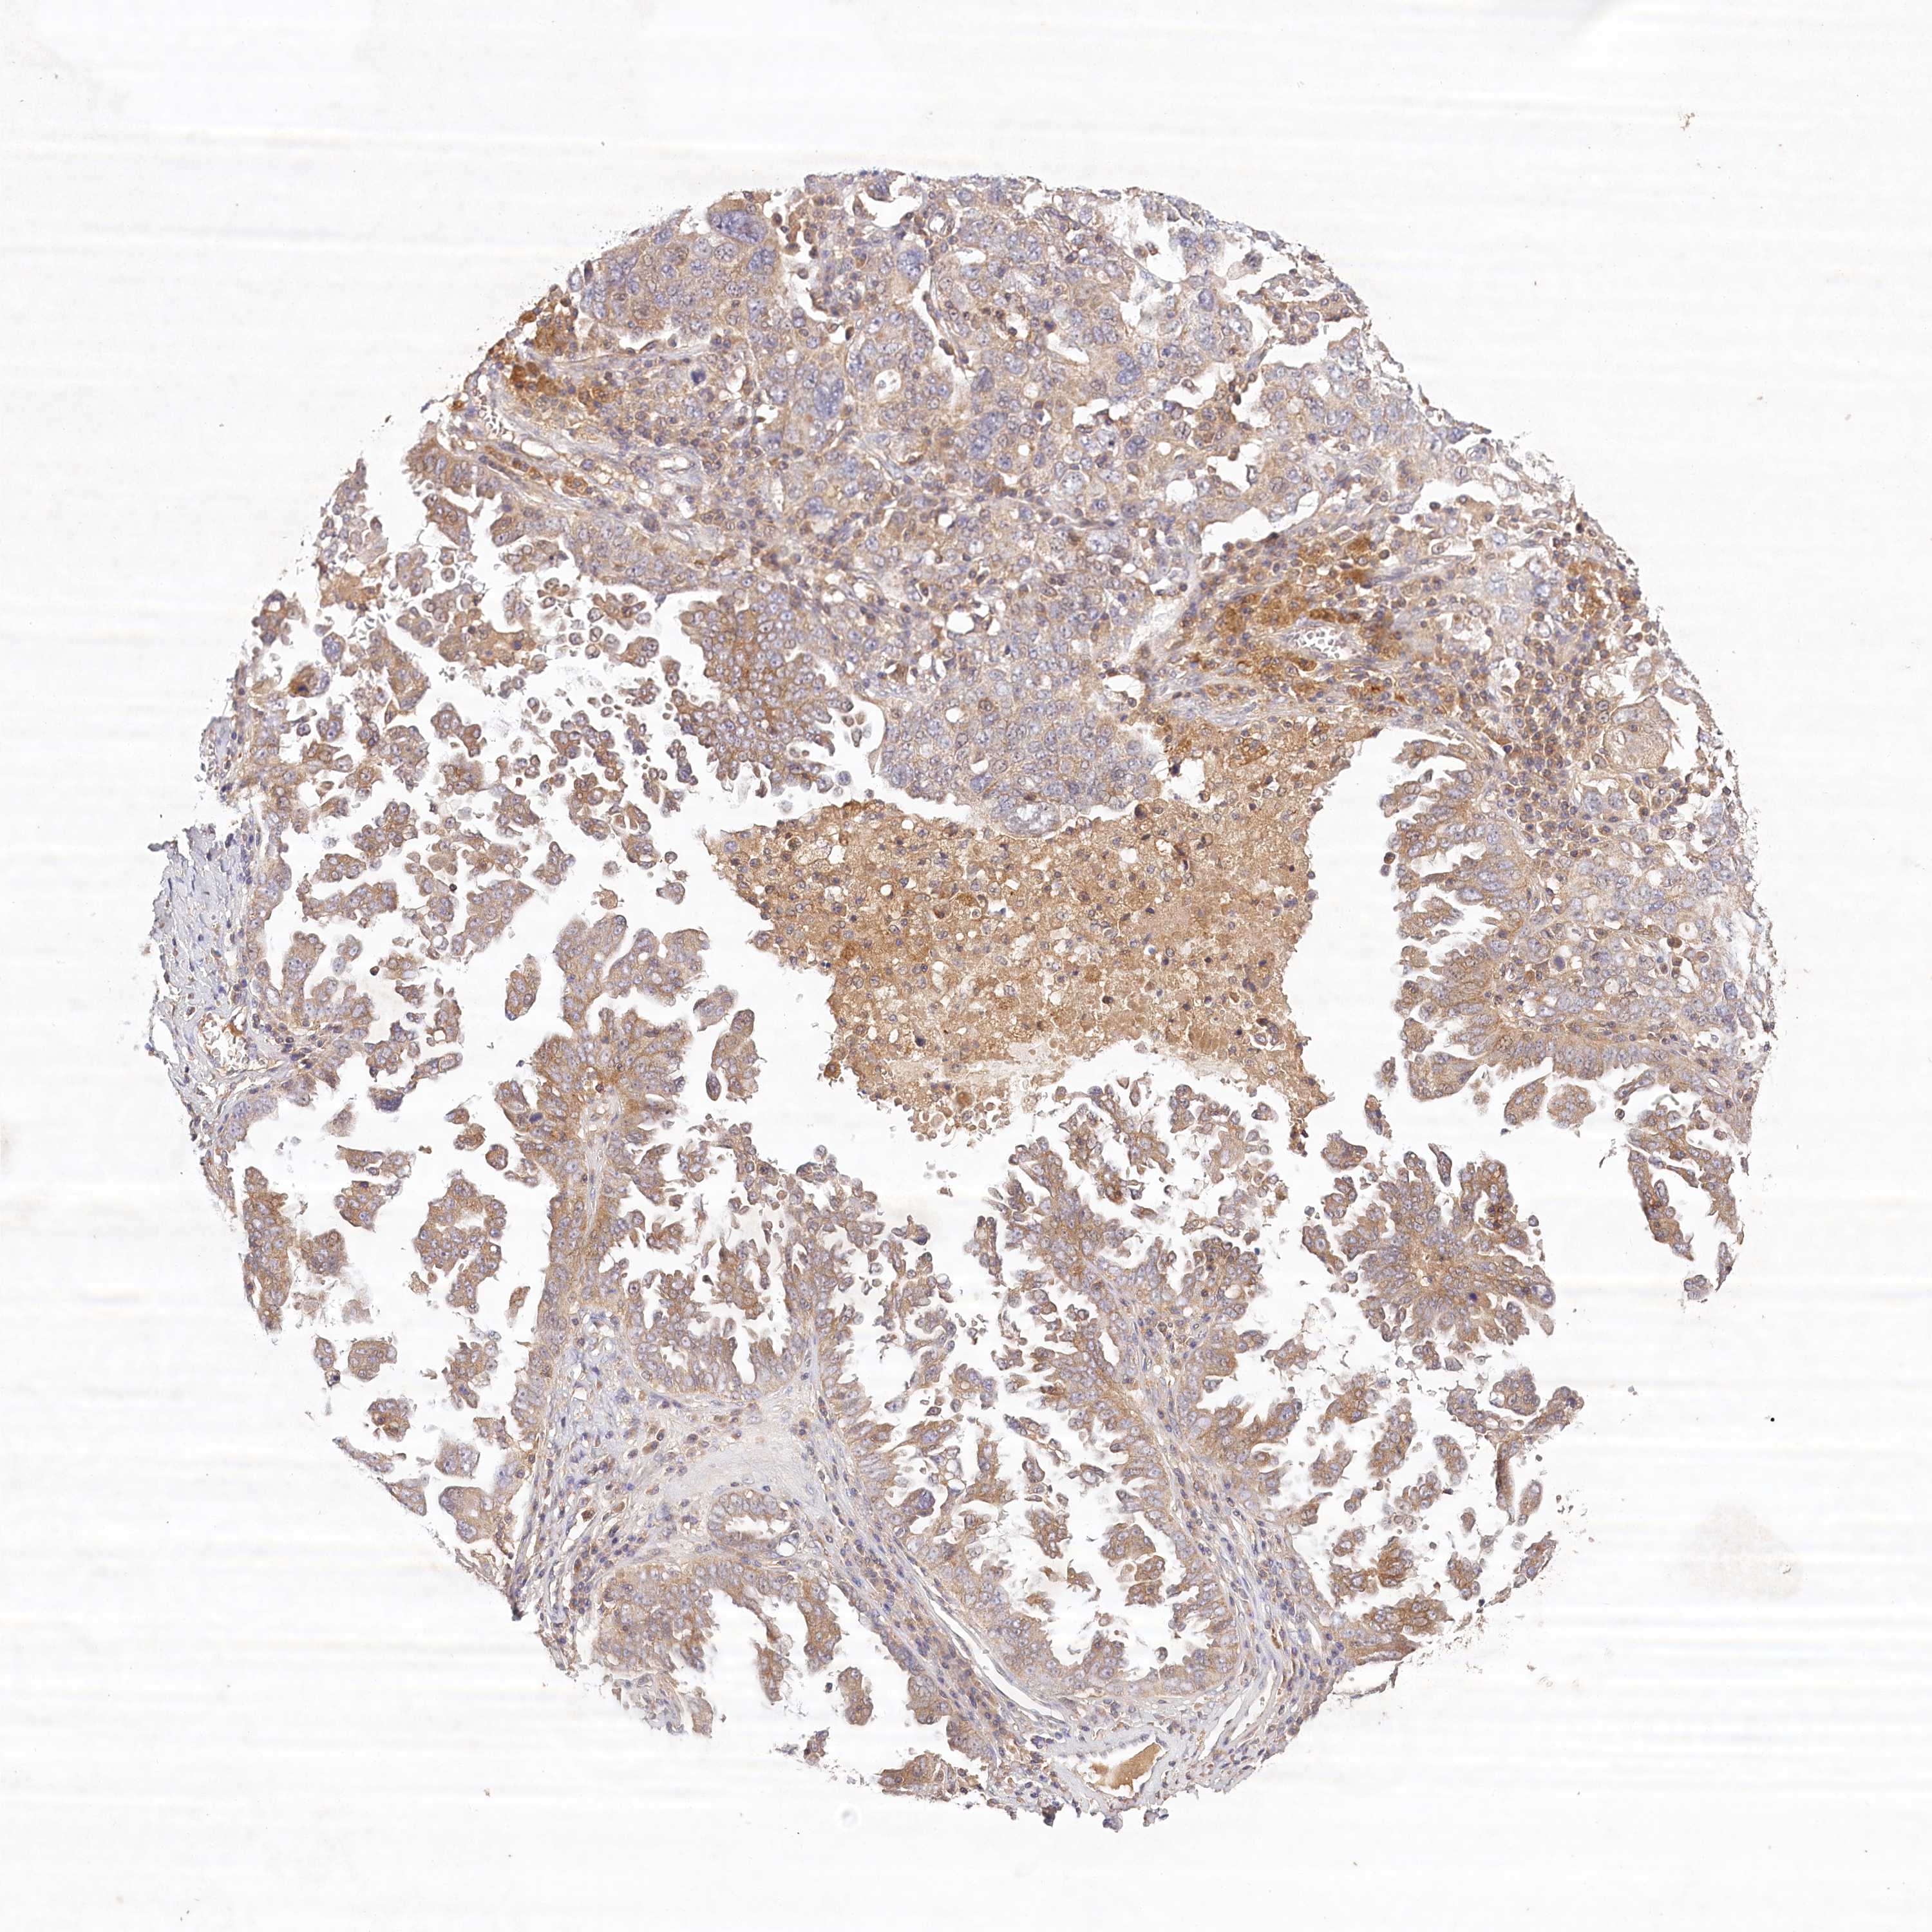

OVARIAN CANCER - Protein expressioni

A mouse-over function shows sample information and annotation data. Click on an image to view it in a full screen mode. Samples can be filtered based on level of antibody staining by selecting one or several of the following categories: high, medium, low and not detected. The assay and annotation is described here.

Note that samples used for immunohistochemistry by the Human Protein Atlas do not correspond to samples in the TCGA dataset.

Antibody stainingi

Antibody staining in the annotated cell types in the current human tissue is reported as not detected, low, medium, or high, based on conventional immunohistochemistry profiling in selected tissues. This score is based on the combination of the staining intensity and fraction of stained cells.

Each image is clickable and will lead to virtual microscopy that enables deeper exploration of all samples and also displays staining intensity scores, fraction scores and subcellular localization as well as patient and tissue information for each sample.

Antibody HPA032060

Antibody HPA032062

Antibody CAB034116

Staining

High

Medium

Low

Not detected

Cystadenocarcinoma, serous, NOS

Carcinoma, endometroid

Cystadenocarcinoma, mucinous, NOS

Carcinoma, NOS